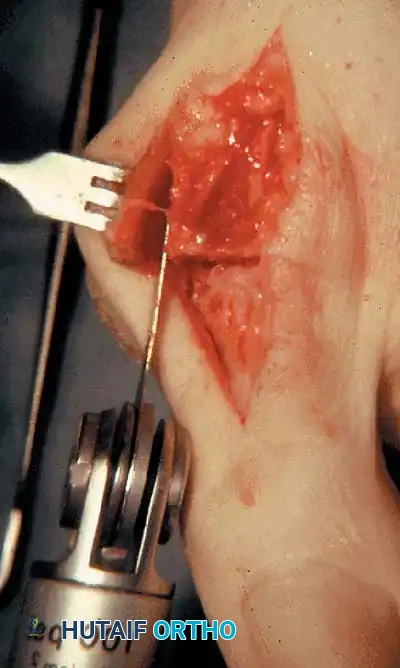

• Using a Freer elevator or a small osteotome for its strength, mobilize the fi bular sesamoid (Fig. 78-31A to C). This may be diffi cult in elderly patients with signifi cant deformity and adherence of the sesamoid to the metatarsal head. Lift the metatarsal dorsally for exposure (Fig. 78-31D and E).

Fig. 78-31 Excision of fi bular sesamoid in modifi ed Keller procedure. With base of proximal phalanx removed and medial eminence excision, exposure of fi bular sesamoid is not as diffi cult from medial incision. A, Operative photograph showing elevation of fi rst metatarsal with strong two-tooth retractor and use of small osteotome to mobilize fi bular sesamoid and lateral capsuloligamentous (frequently contracted) structures. Osteotome is between metatarsal head and lateral sesamoid. When mobilization of fi bular sesamoid is complete, entire sesamoid is visible for excision. Note chondromalacia of tibial sesamoid articular surface medial to osteotome. B, Fibular sesamoid has been excised, and lateral capsular structures and conjoined tendon (in forceps) have been released. Neurovascular bundle to lateral side of hallux is adjacent to these structures. C, Diagrammatic representation of modifi ed Keller procedure. By excising fi bular sesamoid, valgus moment of conjoined tendon of fl exor hallucis brevis and adductor hallucis no longer pulls fl exor hallucis longus tendon laterally (carrying hallux with it) through capsulosesamoid plantar plate and pulley system. D, Metatarsal head must be lifted dorsally to excise fi bular sesamoid under direct vision. E, Note exposure of fi bular sesamoid after mobilization of metatarsal head. Continued